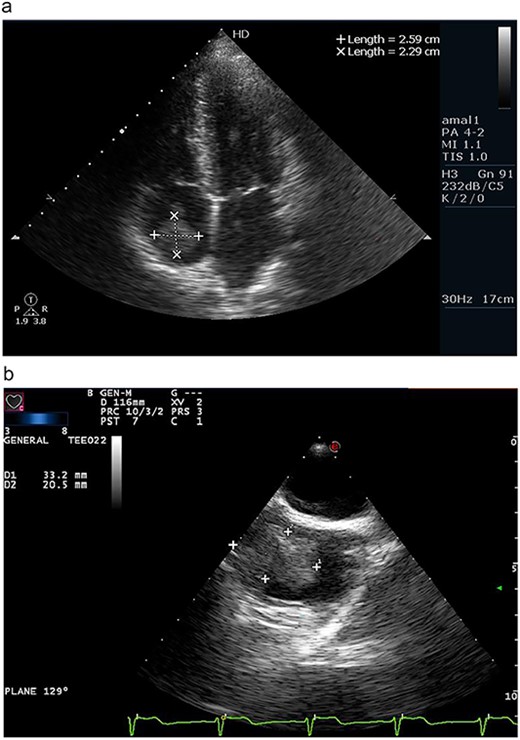

(a) Apical four chamber view on transthoracic echocardiography revealing a right atrial mass measuring 2.59 × 2.29 cm. (b) Transesophageal echocardiography confirming the presence of wide-based, irregular and lobulated right atrial mass measuring 3.32 × 2.05 cm.

On transesophageal echocardiography, the mass appeared lobulated, attached to the right atrial wall and containing multiple foci of calcifications (Fig. 1b).